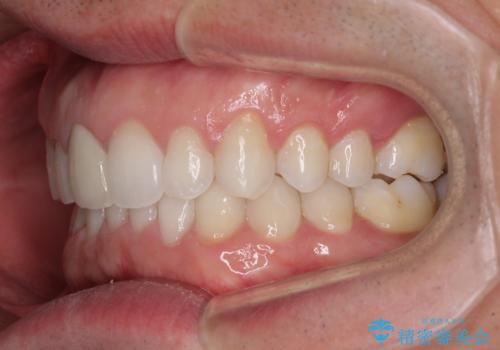

口が閉じにくい インビザラインによる矯正治療

- 口の閉じにくさを気にして来院された患者様です。

患者様と相談の上、横顔の印象から抜歯矯正は必要ないと判断し、IPR(歯と歯の間)並びに歯列全体の後方移動により口元の突出感の改善することとしました。

しっかりと装着時間を守り、ゴムかけも徹底していただいたので、思いの外口元を引っ込めることができました。

これ以上の改善を望まれましたが、非抜歯矯正でこれ以上口元を引っ込めると食いしばりすやすい咬合となるため、この歯列で終了としました。